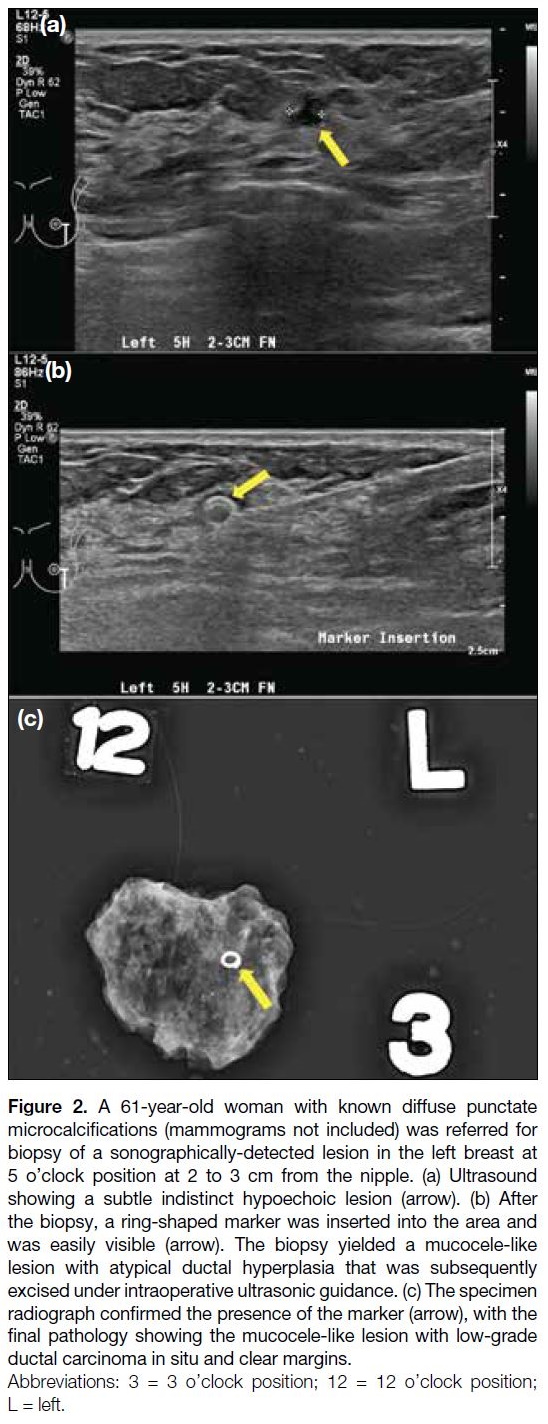

sonographically visible clip marker, which is either of a

special shape (Figure 2) or associated with bioabsorbable

material (Figure 3), to make it easily visible with ultrasound.

Figure 2. A 61-year-old woman with known diffuse punctate

microcalcifications (mammograms not included) was referred for

biopsy of a sonographically-detected lesion in the left breast at

5 o’clock position at 2 to 3 cm from the nipple. (a) Ultrasound

showing a subtle indistinct hypoechoic lesion (arrow). (b) After

the biopsy, a ring-shaped marker was inserted into the area and

was easily visible (arrow). The biopsy yielded a mucocele-like

lesion with atypical ductal hyperplasia that was subsequently

excised under intraoperative ultrasonic guidance. (c) The specimen

radiograph confirmed the presence of the marker (arrow), with the

final pathology showing the mucocele-like lesion with low-grade

ductal carcinoma in situ and clear margins.